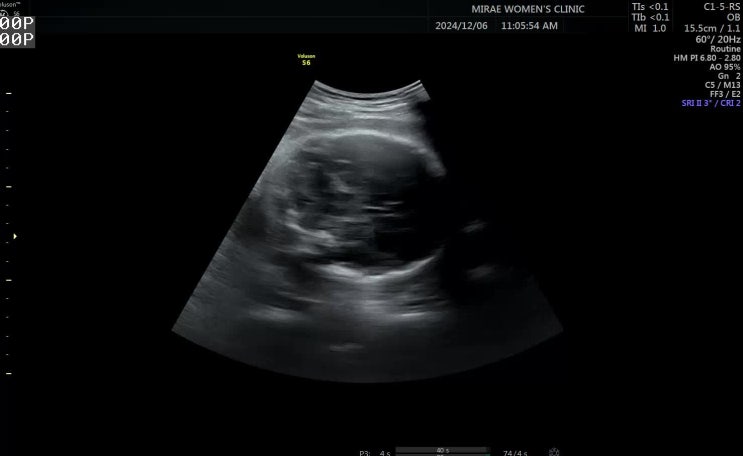

임신 34주차, 35주차 막달검사

안녕하세요 이제 매주 병원을 갑니다 귀찮아.... 임신초기에는 매주가고싶어서 난리였는데 배가 불러서인지...

임신 32주차 정기검진, 33주차 허리통증

안녕하세요 저는 아직도 입덧중입니다 약을 끊어보려했지만 양치덧과 토덧의 늪 또 포기하고 병원간김에 약...